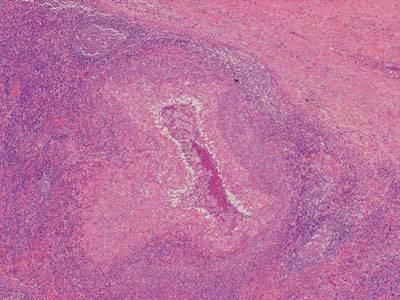

Сифилис

Не менее опасной инфекцией, передающейся половым путем является сифилис. Может буквально тлеть долгие годы в теле человека, а он не знать об этом.

Скрытый период составляет от 21 до 28 дней с момента заражения. Иногда короче от 10 до 15 дней, иногда от 2 до 3 месяцев. Все зависит от здоровья зараженного человека.

Вызван бледной спирохетой (трепонема). Передается при сексе, хватает банального трения и проникновение через мелкие трещинки.

— Через неделю увеличиваются близлежащие лимфатические узлы. Появляется в первичном периоде слабость, недомогание, иногда повышается немного температура и по всему телу появляется сыпь — розовые пятна, иногда в виде эрозий и узелков.